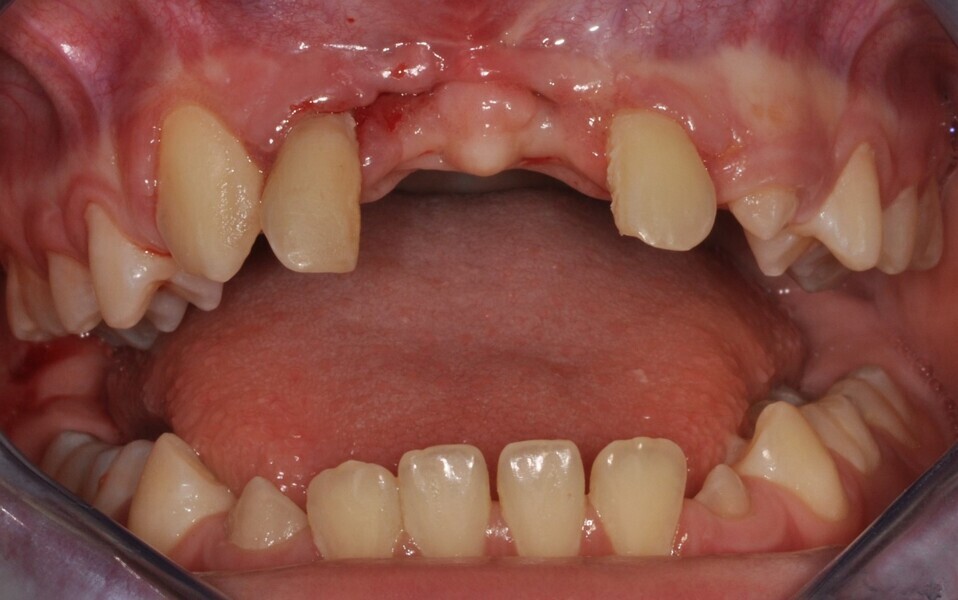

Ryc. 1_Stan miejscowy przed ekstrakcja zębów 11 i 21.